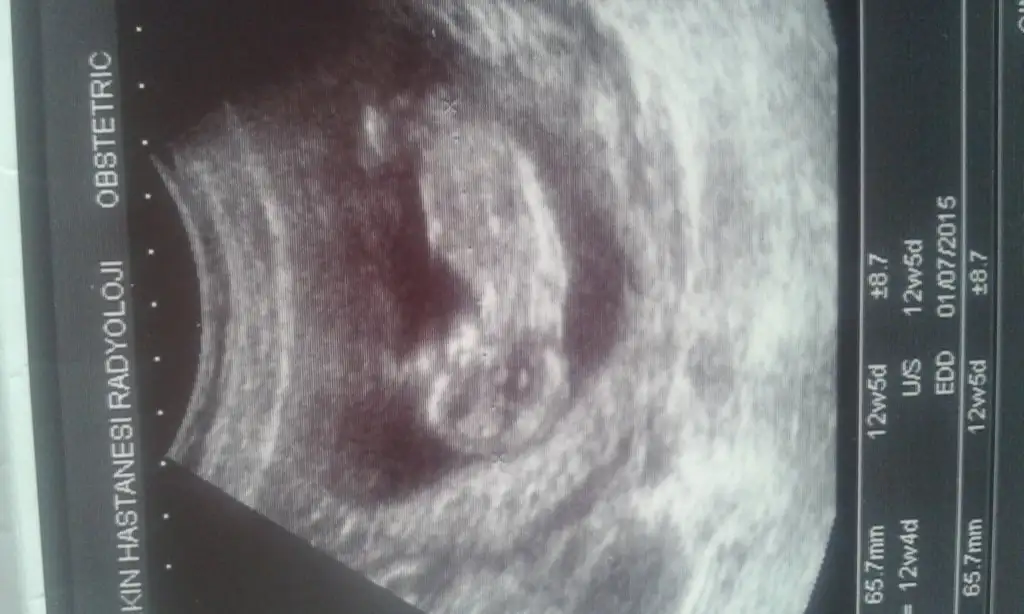

kızlar sizce benmki kızmı erkekmi tam erkek gbi değil derecesi ama kız gbide değil sanki ya :D çözemedm var bsy orda ama IMG_20141230_131619.webp

Hanımlar benim bebişe de bi bakın. 20. Haftayı beklicem. İki dr farklı cinsiyet ssöyledi. Bbakalım sizler ne yorum yaparsınız

Kizlar merhaba daha oncede sordum ama kimse cevap vermedi benim bebegime de yorum yaparmisiniz